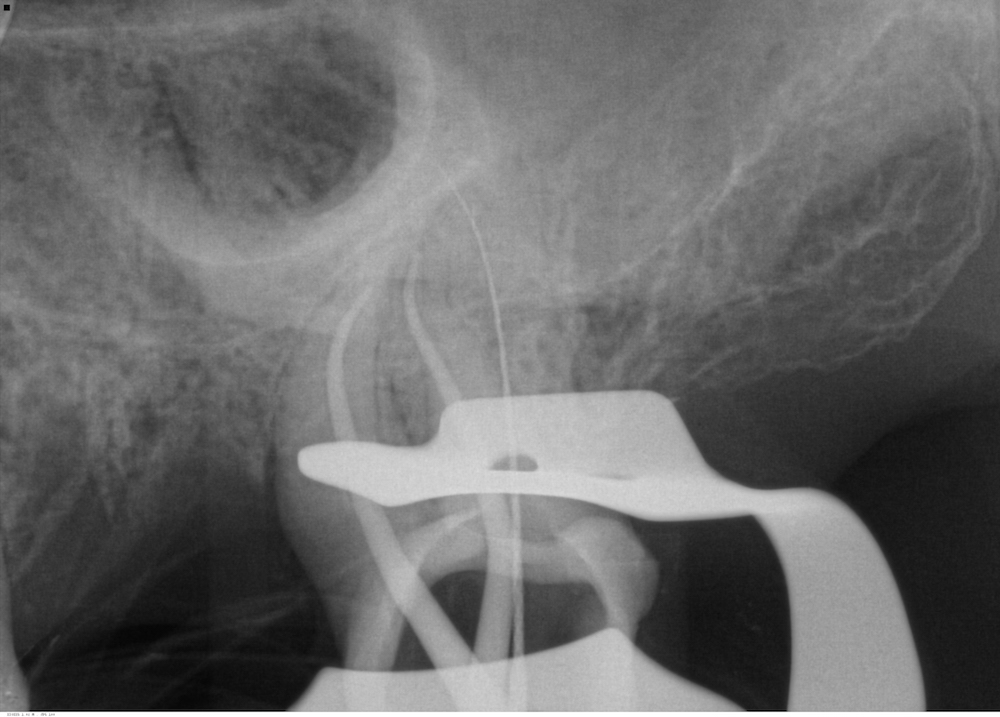

La tête de fragment est découverte à l’aide de limes U (taille 15/20) dégageant un diamètre de 0.5mm seulement. On glisse ensuite une boucle ajustable de fil autour du fragment.

Une fois serrée autour du fragment, celui-ci est extrait en tirant sur le fil.

On ne doit augmenter la taille de la préparation que pour des fragments très rétentifs. Mais même en pareille situation, la préparation est bien moindre que ce qu’elle serait en utilisant des ultrasons ou tout autre méthode. On pourra même utiliser cette méthode sans crainte d’extrusion pour extraire des fragments situés dans la zone périapicale.